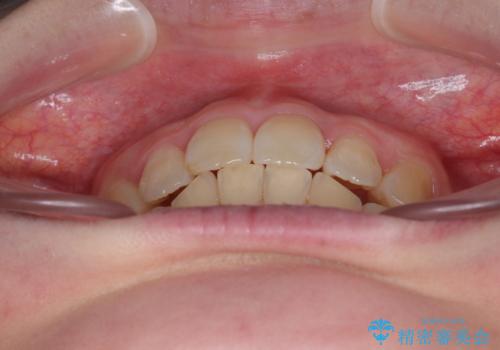

飛び出した前歯 抜歯矯正で横顔が劇的変化

- 飛び出した上顎前歯を気にして来院された患者様です。

下顎は左右2番目の歯が2本欠損しており、上下前歯の前後的な位置は著しくずれている状態でした。

骨格的にも上顎骨が前突傾向にあり、極端な過蓋咬合になっていました。